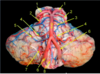

Label 5, 6 & 7

1 - superior temporal gyrus;

2 - inferior frontal gyrus; 3 - insular cortex;

4 - temporal stem;

5 - internal capsule;

6 - thalamus;

7 - lentiform nucleus (the internal and external globus pallidus and the putamen)

8 - frontal horn;

9 - superior circular sulcus;

10 - inferior circular sulcus.

What type of posturing is this person displaying? [1]

1 - superior temporal gyrus; 2 - inferior frontal gyrus; 3 - insular cortex; 4 - temporal stem; **5 - internal capsule;** **6 - thalamus;** **7 - lentiform nucleus** (the internal and external globus pallidus and the putamen) 8 - frontal horn; 9 - superior circular sulcus; 10 - inferior circular sulcus.